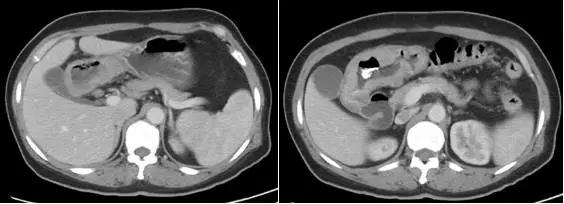

图1 2014年8月腹部CT